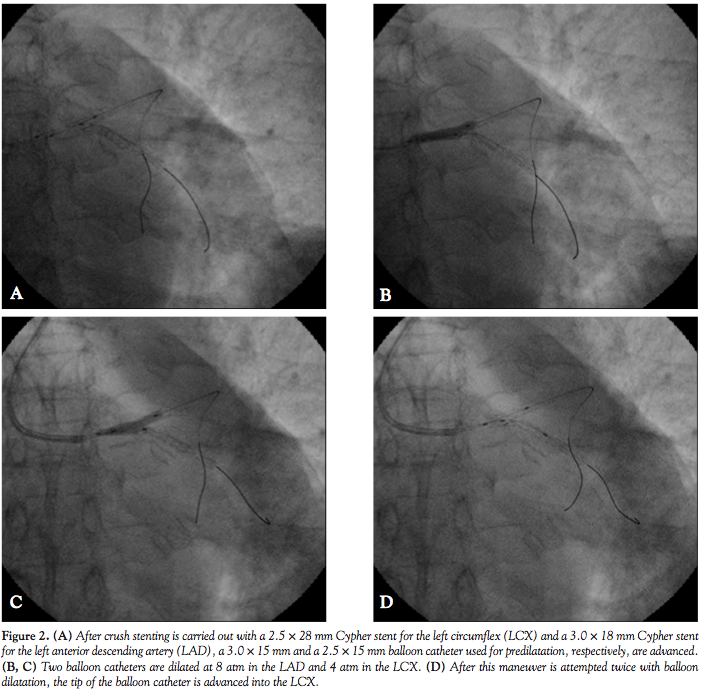

BuddyBalloon Technique for Final KissingBalloon Dilatation After Crush Stenting of the Left Kissing Balloon Technique In the “kissing balloon” technique, two guiding catheters are positioned in the sinus of valsalva and alternatively in the coronary ostium. A guidewire and balloon catheter are introduced into each of the bifurcation vessels. Kissing balloon (kb) inflation was the first specific bifurcation technique to have been developed for percutaneous bifurcation. Kissing stent reconstruction is a widely used technique for. Kissing Balloon Technique.

BuddyBalloon Technique for Final KissingBalloon Dilatation After Crush Stenting of the Left Kissing Balloon Technique Kissing stent reconstruction is a widely used technique for the management of aortoiliac occlusive disease involving the aortic. In the “kissing balloon” technique, two guiding catheters are positioned in the sinus of valsalva and alternatively in the coronary ostium. Kissing balloon (kb) inflation was the first specific bifurcation technique to have been developed for percutaneous bifurcation. The two balloons can. Kissing Balloon Technique.